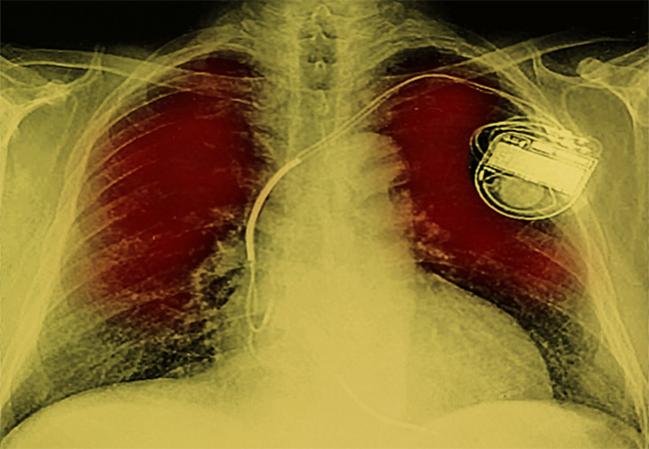

Three new studies suggest that conduction abnormalities leading to permanent pacemaker implantation remain a frequent occurrence after TAVR that can be predicted by various patient, procedural, and clinical characteristics, with one analysis suggesting that patients requiring pacing are more likely to die in the first year after the procedure.

Overall, 6.7% of patients required permanent pacemaker implantation within 30 days of the procedure, with a higher rate observed in those receiving the self-expanding CoreValve prosthesis (Medtronic) versus the balloon-expandable Sapien valve (Edwards Lifesciences; 25.1% vs 4.3%; P < 0.001).

Pacemaker implantation was more frequent with older age and in patients who had a prior conduction defect or received a self-expanding valve. A prior aortic valve procedure, home oxygen use, and longer procedure time were all associated with a lower likelihood of needing permanent pacing.